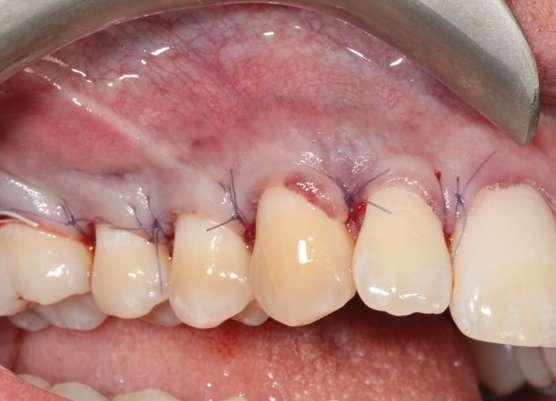

Después de un detallado análisis y valoración de las alternativas terapéuticas, se planificaron 2 procedimientos quirúrgicos mediante colgajos de avance coronal con acceso lateral y sin descargas para el tratamiento de las recesiones del maxilar superior (Fig. 2) (7-9).

A continuación procederemos a describir el paso a paso del tratamiento quirúrgico de las recesiones (Figs. 2 a 7). Ambos procedimientos quirúrgicos se realizaron bajo anestesia local y sedación consciente por vía endovenosa y con un tiempo de descanso para el paciente entre procedimientos de 1 mes y medio. En este caso, el eje de rotación fueron los caninos en ambos lados y todas las incisiones para-marginales oblicuas (líneas punteadas en rojo) se realizaron hacia estos dientes (Fig. 2).

Figura 1: Situación inicial. Obsérvese la recesión gingival profunda en 1.3 y 2.3, así como la erosión gingival y el borrado de la línea amelocementaria debido al cepillado agresivo.

caso clínicoCIRUGÍA BUCAL

los dientes 1.5, 2.4 y 2.5 para garantizar una correcta adaptación del

Figura 2. Planificación quirúrgica.

Figura 4. Diseño de las incisiones y del colgajo. Nótese la creación de una “falsa recesión” en

colgajo al finalizar el avance coronal.

Figura 3. Situación clínica el día de la intervención quirúrgica.

Figura 5. Colgajo elevado “Split-Full-Split” y fijación de los injertos de tejido conectivo con suturas 7/0 reabsorbibles (PGA).

Figura 7. Post-operatorio y excelente curación 7 días después de la cirugía.

Figura 6. Avance coronal sin tensión y sutura del colgajo mediante puntos “sling” con sutura 6/0 reabsorbible (PGA).